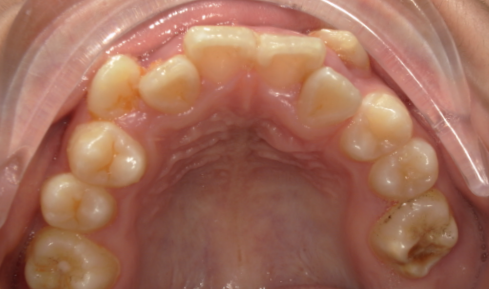

我们的颌骨就像一栋“牙齿公寓”,每颗牙齿都需要固定的“居住面积”。但由于遗传、发育等因素,不少人的“公寓”面积先天不足:颌骨长度或宽度不够,而牙齿的数量和大小却没减少。这就会导致牙齿挤在狭小的空间里,出现拥挤不齐(比如牙齿重叠、扭转)、门牙前突(嘴唇闭不上、侧面看嘴型突出)等问题。

这是最常见的需求。中度以上的牙齿拥挤(比如拥挤度>4mm),单纯靠扩弓(扩大牙弓宽度)往往无法获得足够空间,强行排列可能导致牙齿受力过大、牙根吸收,甚至变成整齐的龅牙。此时拔牙(多为智齿、双尖牙,可被替代功能的牙齿),能快速释放空间,让拥挤的牙齿顺利排齐,同时保证每颗牙齿的排列角度、间距都符合生理标准。